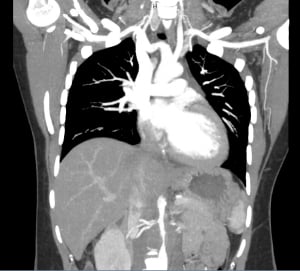

Patient underwent CT angiogram of her chest and abdomen emergently and the findings were suspicious for “periaortitis in association with midaortic syndrome with severe stenosis/near occlusion of the infrarenal aorta, bilateral renal arteries, celiac trunk, and SMA.” Findings that could represent a vasculitis versus neoplastic process.

Narrowing of aorta recon

Thickened aorta on CT